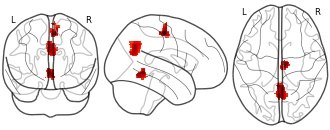

"name": "Multi_VBMsmaller_fMRIdecreased",

"description": "Multi-modal analysis in BPD. Brain regions exhibiting smaller gray matter and decreased activation during emotion processing in BPD compared to healthy controls. Note: Results were thresholded at p<.0025. Note2: Results were updated (see Erratum for this publication).",